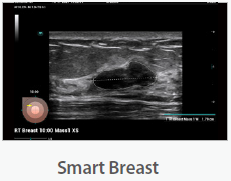

Mindray Ultrasound Consona N9

صور متعلقة